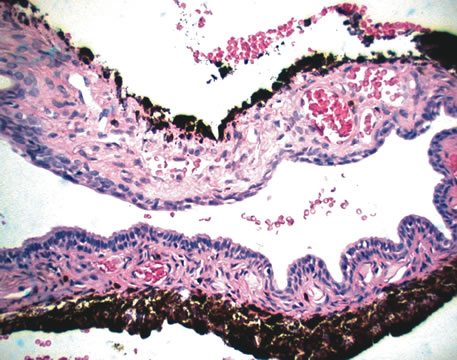

Three histologic patterns of granulomatous inflammation may be seen: diffuse, discrete, and zonal. In diffuse granulomatous inflammation, the epithelioid histiocytes are scattered throughout the involved uveal tissue (Fig. 19). There may be an accompanying background of lymphocytes and plasma cells. Discrete granulomatous inflammation reveals well-circumscribed areas of epithelioid histiocytes (Fig. 20). Zonal granulomatous inflammation consists of a central zone of necrosis and/or polymorphonuclear leukocytes surrounded by epithelioid histiocytes, which is in turn surrounded by a zone of non-granulomatous inflammation consisting of granulation tissue, lymphocytes and plasma cells (Fig. 21).

Fig. 21. Tuberculous choroiditis. A zonal granulomatous inflammation is present. Central area shows necrosis. (Hemotoxylin-eosin ×65.)